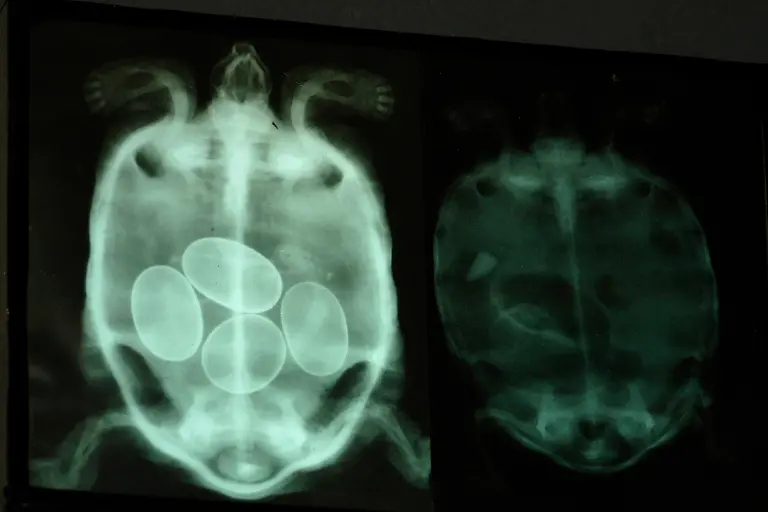

Nägel, Messer, TelefoneWas Röntgenstrahlen zum Vorschein bringen

Nicht immer zeigen Röntgenaufnahmen das, was man von ihnen erwartet. Oft kommt es zu Bildern, die selbst hartgesottene Betrachter zum Schaudern bringen - und der Wissenschaft Rätsel aufgeben.